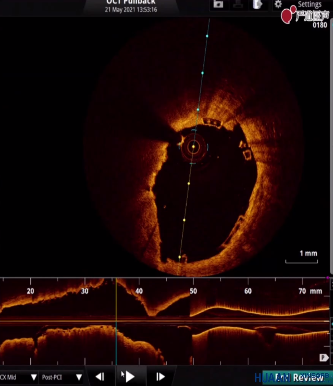

OCT提示11点方向支架贴壁不良

术中,葛均波院士先使用3.0*10mm切割球囊以6-8atm切割LCX狭窄病变,扩张满意之后选择Xinsorb 3.5-18mm可降解支架,精确定位于LCX近段,逐渐缓慢增加压力释放支架,最后以8atm释放支架,但造影提示支架近端左房支对侧管壁支架球囊扩张不充分,有小切记表现,为明确支架贴壁情况,使用OCT进行腔内影像检查评估。OCT检查结果提示,近段病变支架贴壁不良,尤其有分支血管部位。

使用3.5*12mm后扩张球囊对支架远端以14atm进行后扩张,近端以18atm进行后扩张。扩张后,再次复查OCT,虽然用3.5*12mm后扩张球囊打到18atm,支架贴壁情况明显改善,但左房支开口对侧仍有个别支架梁贴壁不佳,但由于后扩张压力已经比较大,其余部位已充分贴壁,故不再反复后扩张。OCT对评估支架贴壁不良起到了很大的帮助。

OCT提示2点方向仍有个别支架梁贴壁不良